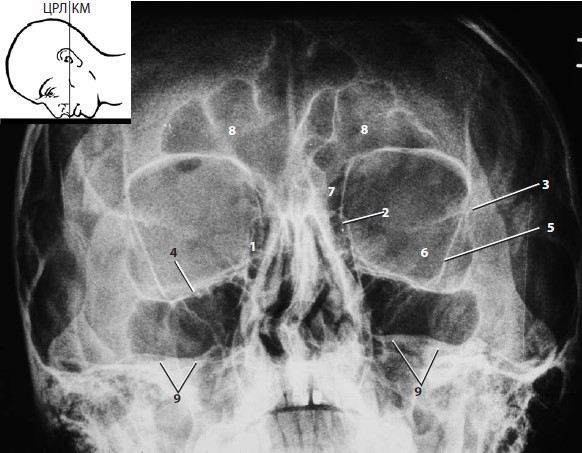

а — носолобная (передняя фронто-окципитальная) проекция Caldwell,

- носолобная (передняя фронтоокципитальная) проекция Caldwell. Лежащий на животе пациент касается кассеты кончиком носа и лбом. Угол между направлением рентгеновского луча и кантомеатальной линией, составляющий 15-23°, уводит тень височной кости книзу от изображения орбиты.

Снимок, полученный при носоподбородочной укладке с плотно прижатым носом, является обзорным изображением глазниц в прямой проекции, позволяющим сравнить форму и размеры margo orbitalis. Кроме того, данная укладка является основной при исследовании лобных, верхнечелюстных пазух и решетчатого лабиринта. Наконец, при носоподбородочной укладке хорошо видны кости лицевого скелета.

Благодаря отведению тени пирамиды височной кости вниз укладка обеспечивает отчетливую визуализацию медиальной (1), нижней (2) и верхней (3) стенок глазниц, подглазничного края (4) и одноименного канала (5), лобно-скулового шва (6), скуловой дуги (7), малого крыла клиновидной кости (8), а также лобных (9), верхнечелюстных пазух (10) и решетчатого лабиринта (11). 12 — безымянная линия (linea innominata); 13 — решетчатая пластинка решетчатой кости; 14 — петушиный гребень